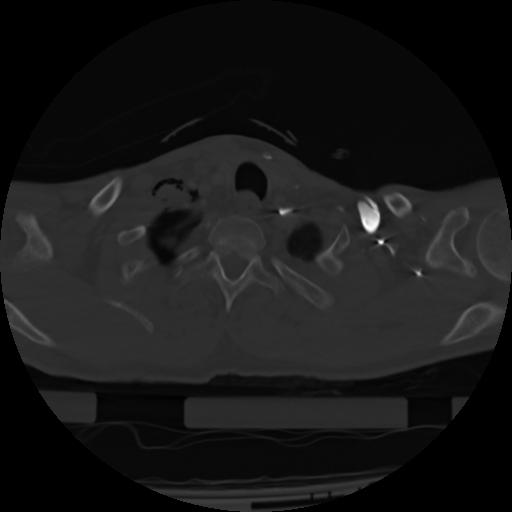

21 ANGIO,CE,Axial,3.0,ANGIO,,